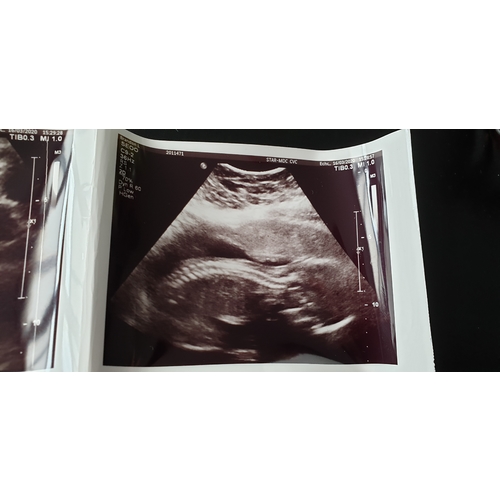

Ik ben hier 16 maart geweest voor de 20 weken echo.. toen mocht mijn man gewoon mee naar binnen. De vrouw die de echo deed was helemaal ingepakt voor de veiligheid. Maar verder was het heel goed te doen.. 1 tip: neem de trap naar boven.. de lift is echt vreselijk.. alsof je elk moment naar beneden kan storten..

Ik moest 24 maart en ben een dag van tevoren gebeld om te vragen of ik geen griepverschijnselen had en om aan te geven dat de partner niet mee mocht. Wil iedereen meegeven hoe rot het ook is om toch er echt van te genieten van het zien van je baby.

Mijn partner is mee gegaan om aan de echoscopist te vragen of het echt niet mag maar het zijn landelijke voorschriften. Op het eind mocht ik wel filmen toen zij rustig nog eens alles naliep en heb extra echo's gehad. Mocht ik wel slecht bericht krijgen mocht ik mijn partner alsnog bellen en zou hij wel naar binnen mogen. Dit was gelukkig niet het geval, erg eigenwijs maar verder perfect.

Veel vrouwen hebben het over videobellen maar ik zou dat afraden gezien je zelf ook goed moet opletten, veel info krijgt, ook wil genieten (voor jou en je partner) en je moet er ontspannen bij liggen. Daarbij is het sowieso een lang onderzoek en ik heb zelfs nog daarna 20 minuten moeten wandelen ivm het gezicht niet willen laten zien en was ik totaal meer dan uur kwijt.